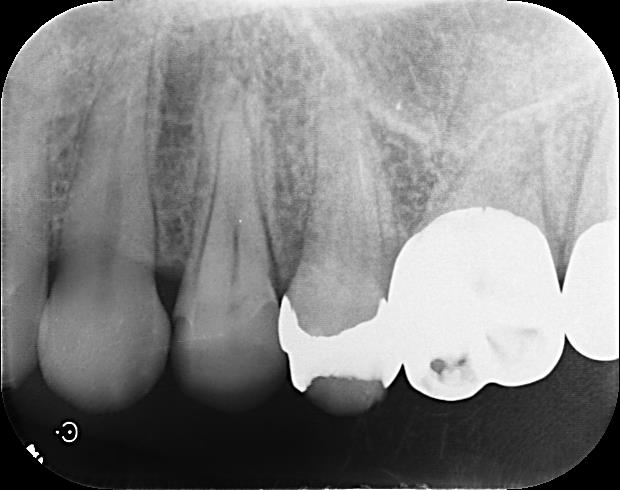

根管治療